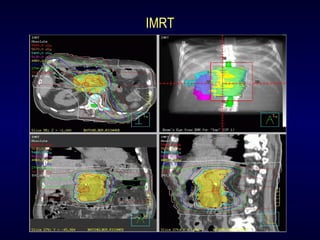

3-D Conformal RT

IMRT

Radiosurgery